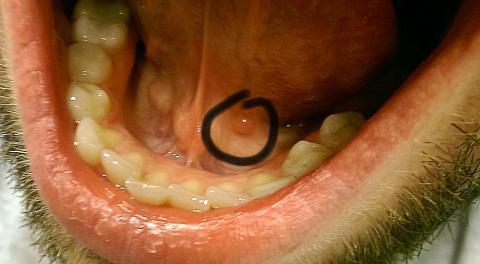

Jozef2 - 5.1.2016 21:26:45 Dobrý deň. Už dlhšiu dobu (asi rok) pozorujem pod jazykom červenú hrčku o veľkosti asi 5mm. Nebolí ma a ani sa nezväčšuje. Prikladám aj fotografiu. Viete mi prosím povedať o čo by sa mohlo jednať ? Ďakujem.

Dobrý den, jde o cystu (tzv. mukokélu), která vznikla ucpáním vývodu malé slinné žlázky v dutině ústní. Ve většině případů zmizí sama, pokud začne dělat obtíže (růst, bolet), navštivte lékaře (stomatolog nebo ORL).